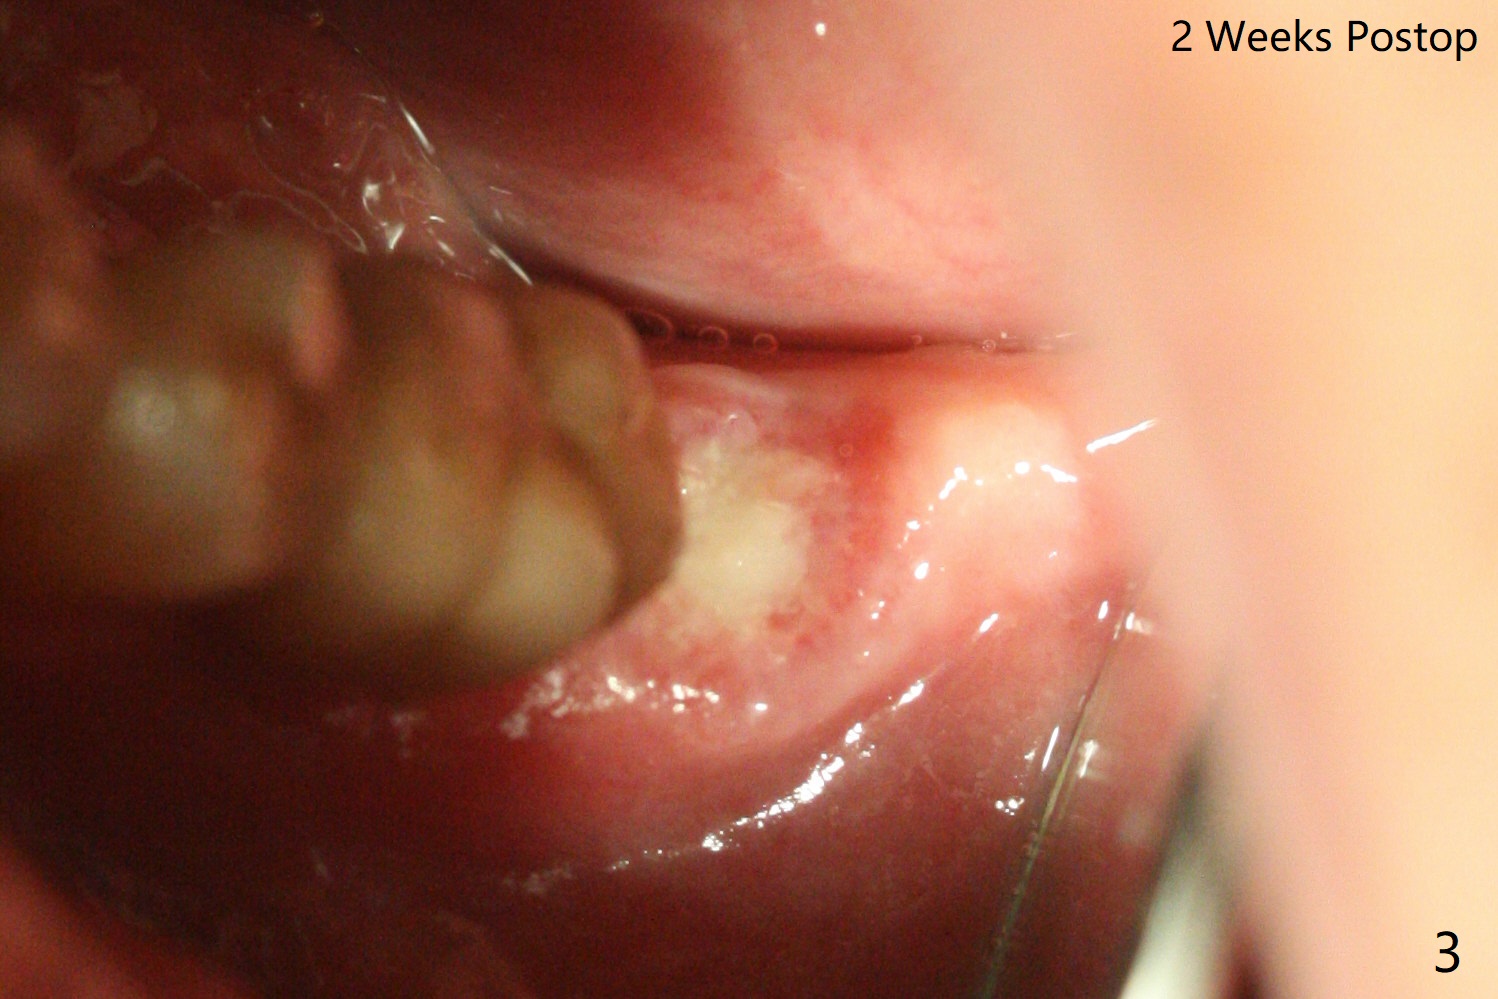

Biopsy punch is used after guide tissue punch marking at #15 because of expected low stability associated with a 8.5 mm long implant for the 73-year-old woman (Fig.1). For #18 site, the same punch is reused with reduced sharpness and some trauma to the tissue. After implant placement (Fig.2), the osteotomy appears to invade the buccal nonkeratinized gingiva. The saved tissue returns to the sites with perio glue fixation and perio dressing. The dressing at #18 is loose 2 weeks postop. When it is removed, the wound seems to be healing (Fig.3). The dressing at #15 remains stable 2 weeks postop (not removed).